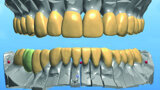

Restoring function and aesthetics with monolithic zirconia restorations